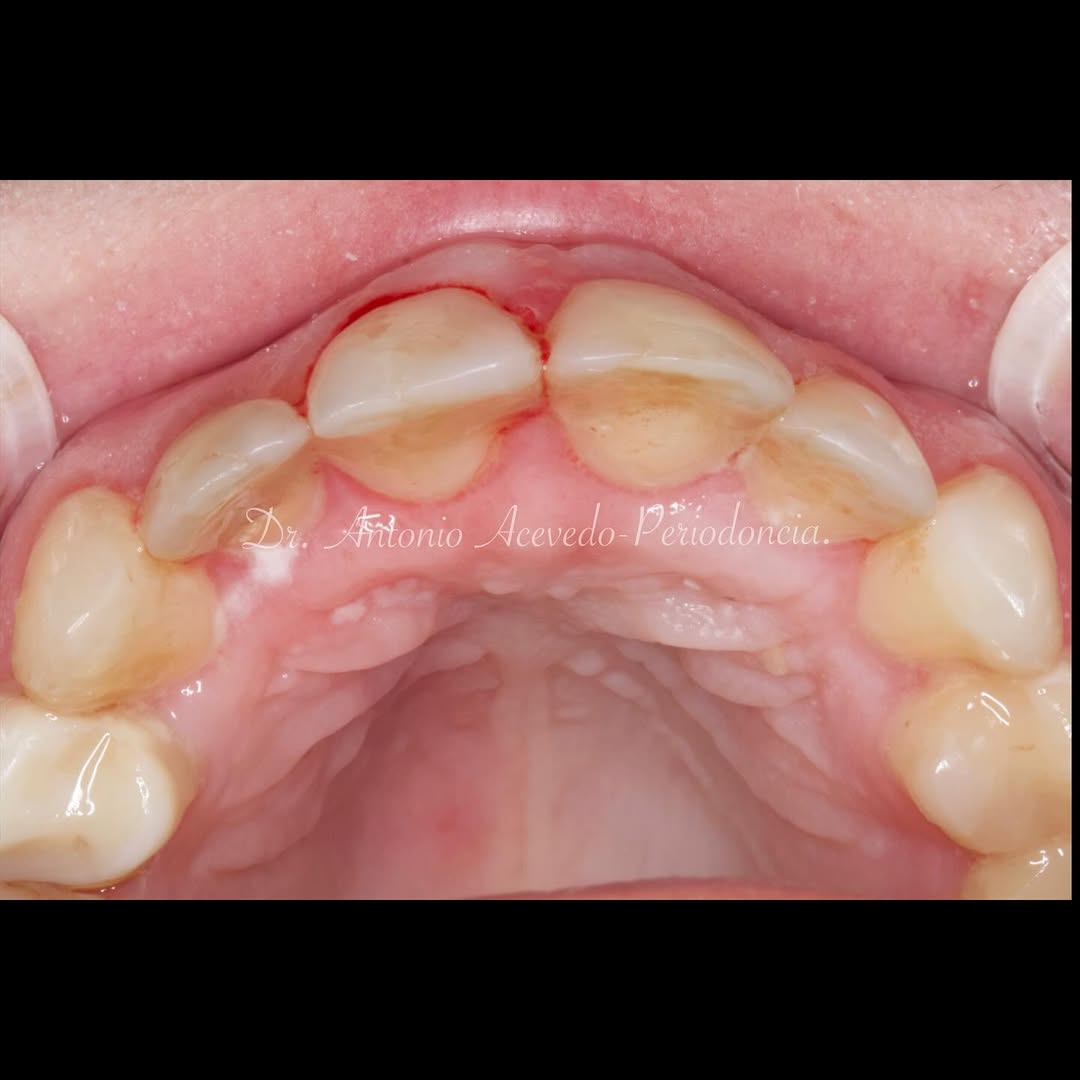

Durante una mañana, asistirás a una Cirugía Mucogingival de recubrimiento radicular de recesiones múltiples en IV y V sextante (36 a 43).

Gracias al uso del microscopio y a la proyección en tiempo real en pantalla, verás exactamente lo mismo que veo yo durante la cirugía, sin tener que estar

Podrás asistir a la planificación de casos y cirugía de injerto de tejido conectivo. Factores determinantes y elección de la técnica adecuada. Sumérgete en un protocolo predecible y técnicamente correcto para obtener resultados óptimos.

Aprende la planificación y técnica de la cirugía Mucogingival para el recubrimiento de recesiones y aumento de banda queratinizada en el sector anteroinferior

Durante una mañana, asistirás a una Cirugía Mucogingival de recubrimiento radicular de una recesión unitaria en 31 con frenillo asociado. Gracias al uso del microscopio y a la proyección en tiempo real en pantalla, verás exactamente lo mismo que veo yo durante la cirugía, sin tener que estar

Una estancia clínica pensada para quienes quieran iniciarse o dar un paso más en el campo de la cirugía mucogingival. Durante esta experiencia tendrás la oportunidad de aprender en directo cómo se planifica y se lleva a cabo una cirugía mucogingival mediante técnica de Túnel.